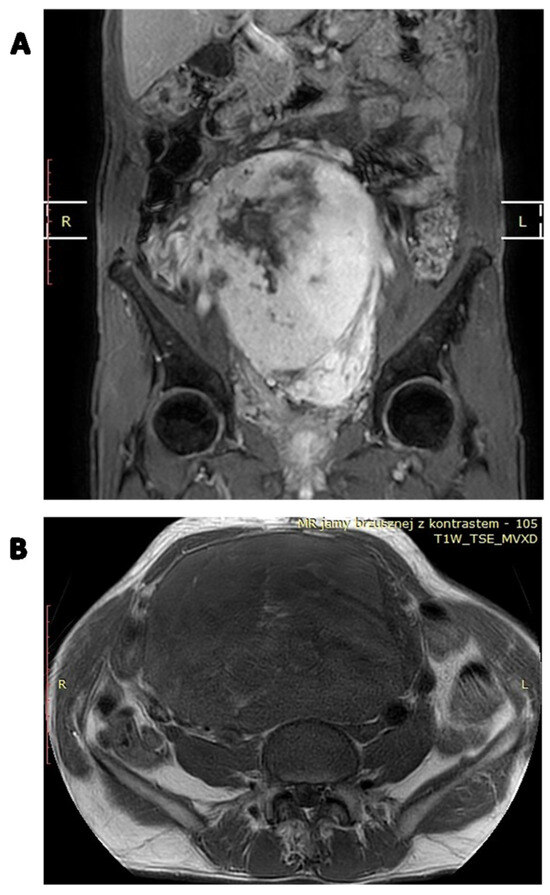

- Zhang, W.D.; Chen, J.Y.; Cao, Y.; Liu, Q.Y.; Luo, R.G. Computed tomography and magnetic resonance imaging findings of solitary fibrous tumors in the pelvis: Correlation with histopathological findings. Eur. J. Radiol. 2011, 78, 65–70. [Google Scholar] [CrossRef]

- Li, X.M.; Reng, J.; Zhou, P.; Cao, Y.; Cheng, Z.Z.; Xiao, Y.; Xu, G.H. Solitary fibrous tumors in abdomen and pelvis: Imaging characteristics and radiologic-pathologic correlation. World J. Gastroenterol. 2014, 20, 5066–5073. [Google Scholar] [CrossRef] [PubMed]

- Shanbhogue, A.K.; Prasad, S.R.; Takahashi, N.; Vikram, R.; Zaheer, A.; Sandrasegaran, K. Somatic and visceral solitary fibrous tumors in the abdomen and pelvis: Cross-sectional imaging spectrum. Radiographics 2011, 31, 393–408. [Google Scholar] [CrossRef] [PubMed]